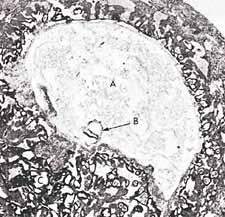

Le deuxième sens du mot alaqah est "une chose suspendue". C'est ce que nous pouvons voir sur les illustrations 2 et 3: l'embryon en suspension dans l'utérus de la mère, au stade de la alaqah.

Illustration 3: Sur cette photomicrographie, nous pouvons voir la suspension d'un embryon (B) au stade de la alaqah (âgé d'environ 15 jours) dans l'utérus de la mère. La grandeur réelle de l'embryon est d'environ 0,6 mm. (The Developing Human (L'humain en développement), Moore, 3e édition., p. 66, adapté de Histology (Histologie), Leeson et Leeson.)